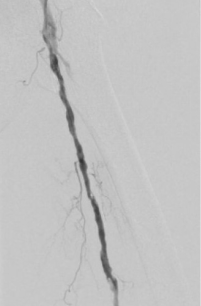

1. 术前造影:

辅助检查:股浅动脉中上段节段性狭窄,下段闭塞,胫前、胫后动脉闭塞,钙化严重。

2. 经鞘置入椎管、CXI、V18导丝正向开通股浅动脉下段,导丝通过,导管无法跟进,经皮穿刺钙化灶,导管跟进造影发现位于内膜下。